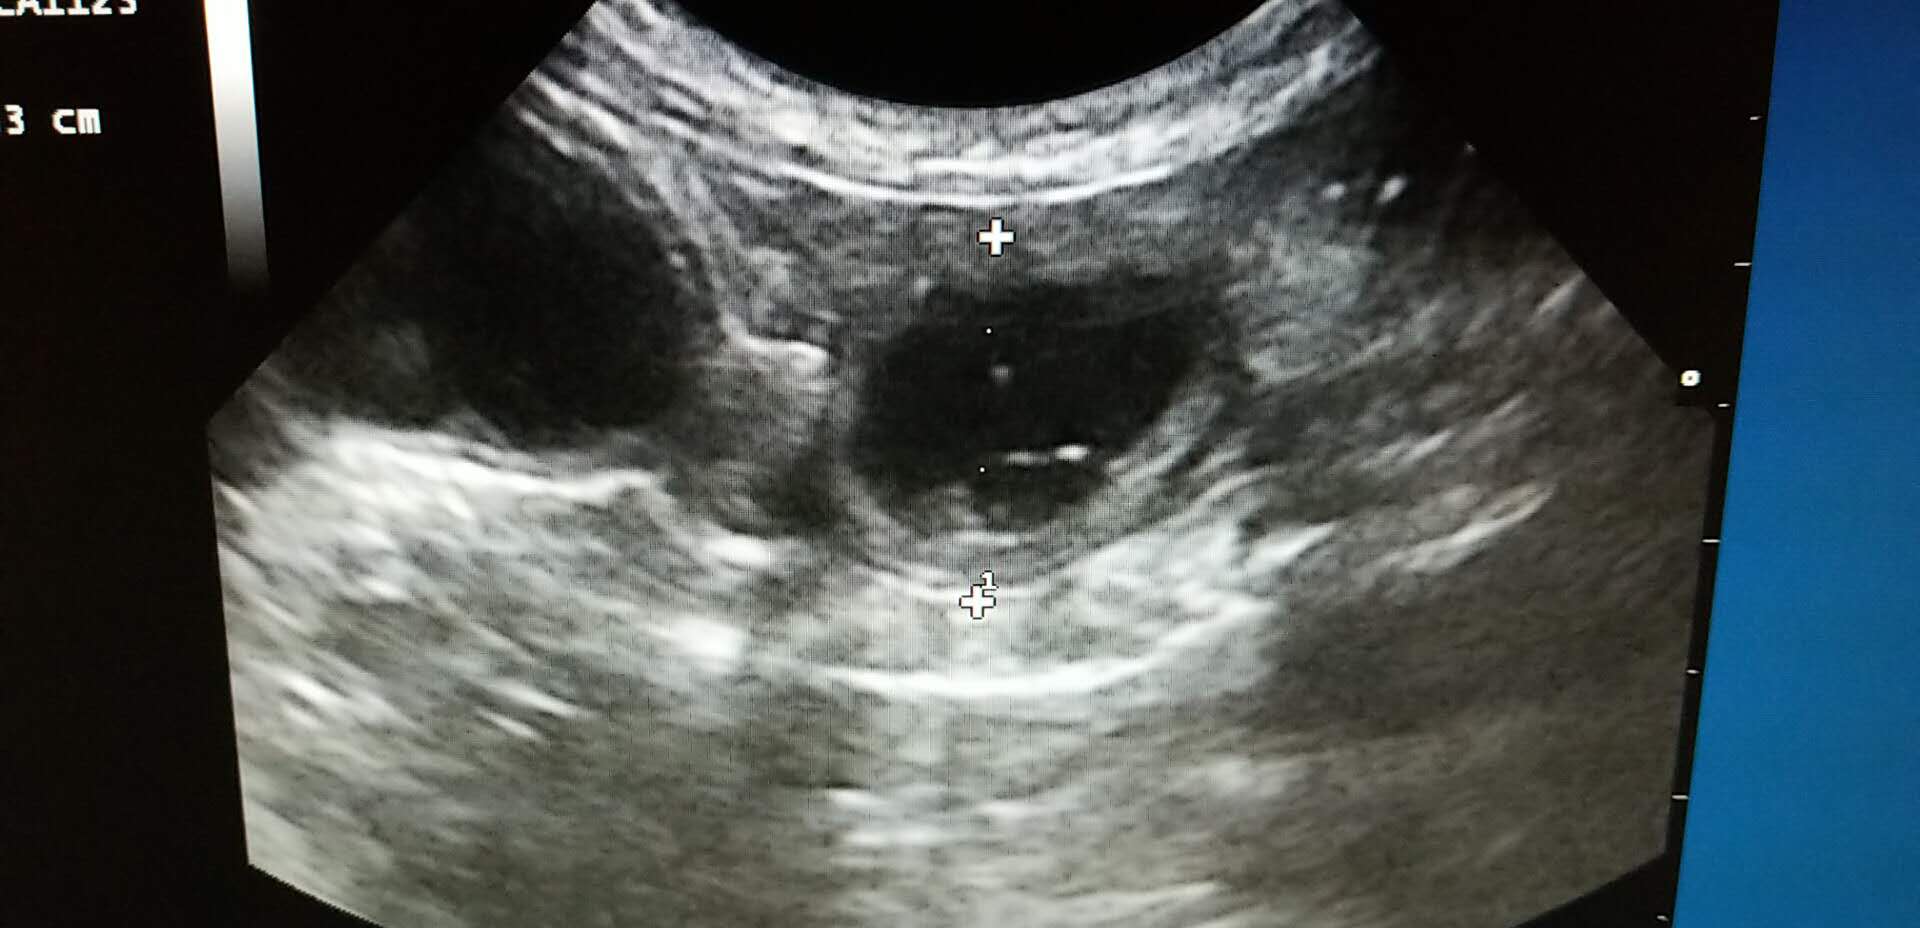

★血液以及影像学检查:血常规提示患猫存在轻度的脱水,生化检查未见明显异常。X-ray提示腹腔存在少量气体,肠腔未见明显异常增大。超声下,可见胃内存在大量的液体,肠腔大量液体,肠道不蠕动,在停止蠕动的肠道段前后扫查,未见明显的异物和肿块。

超声检查